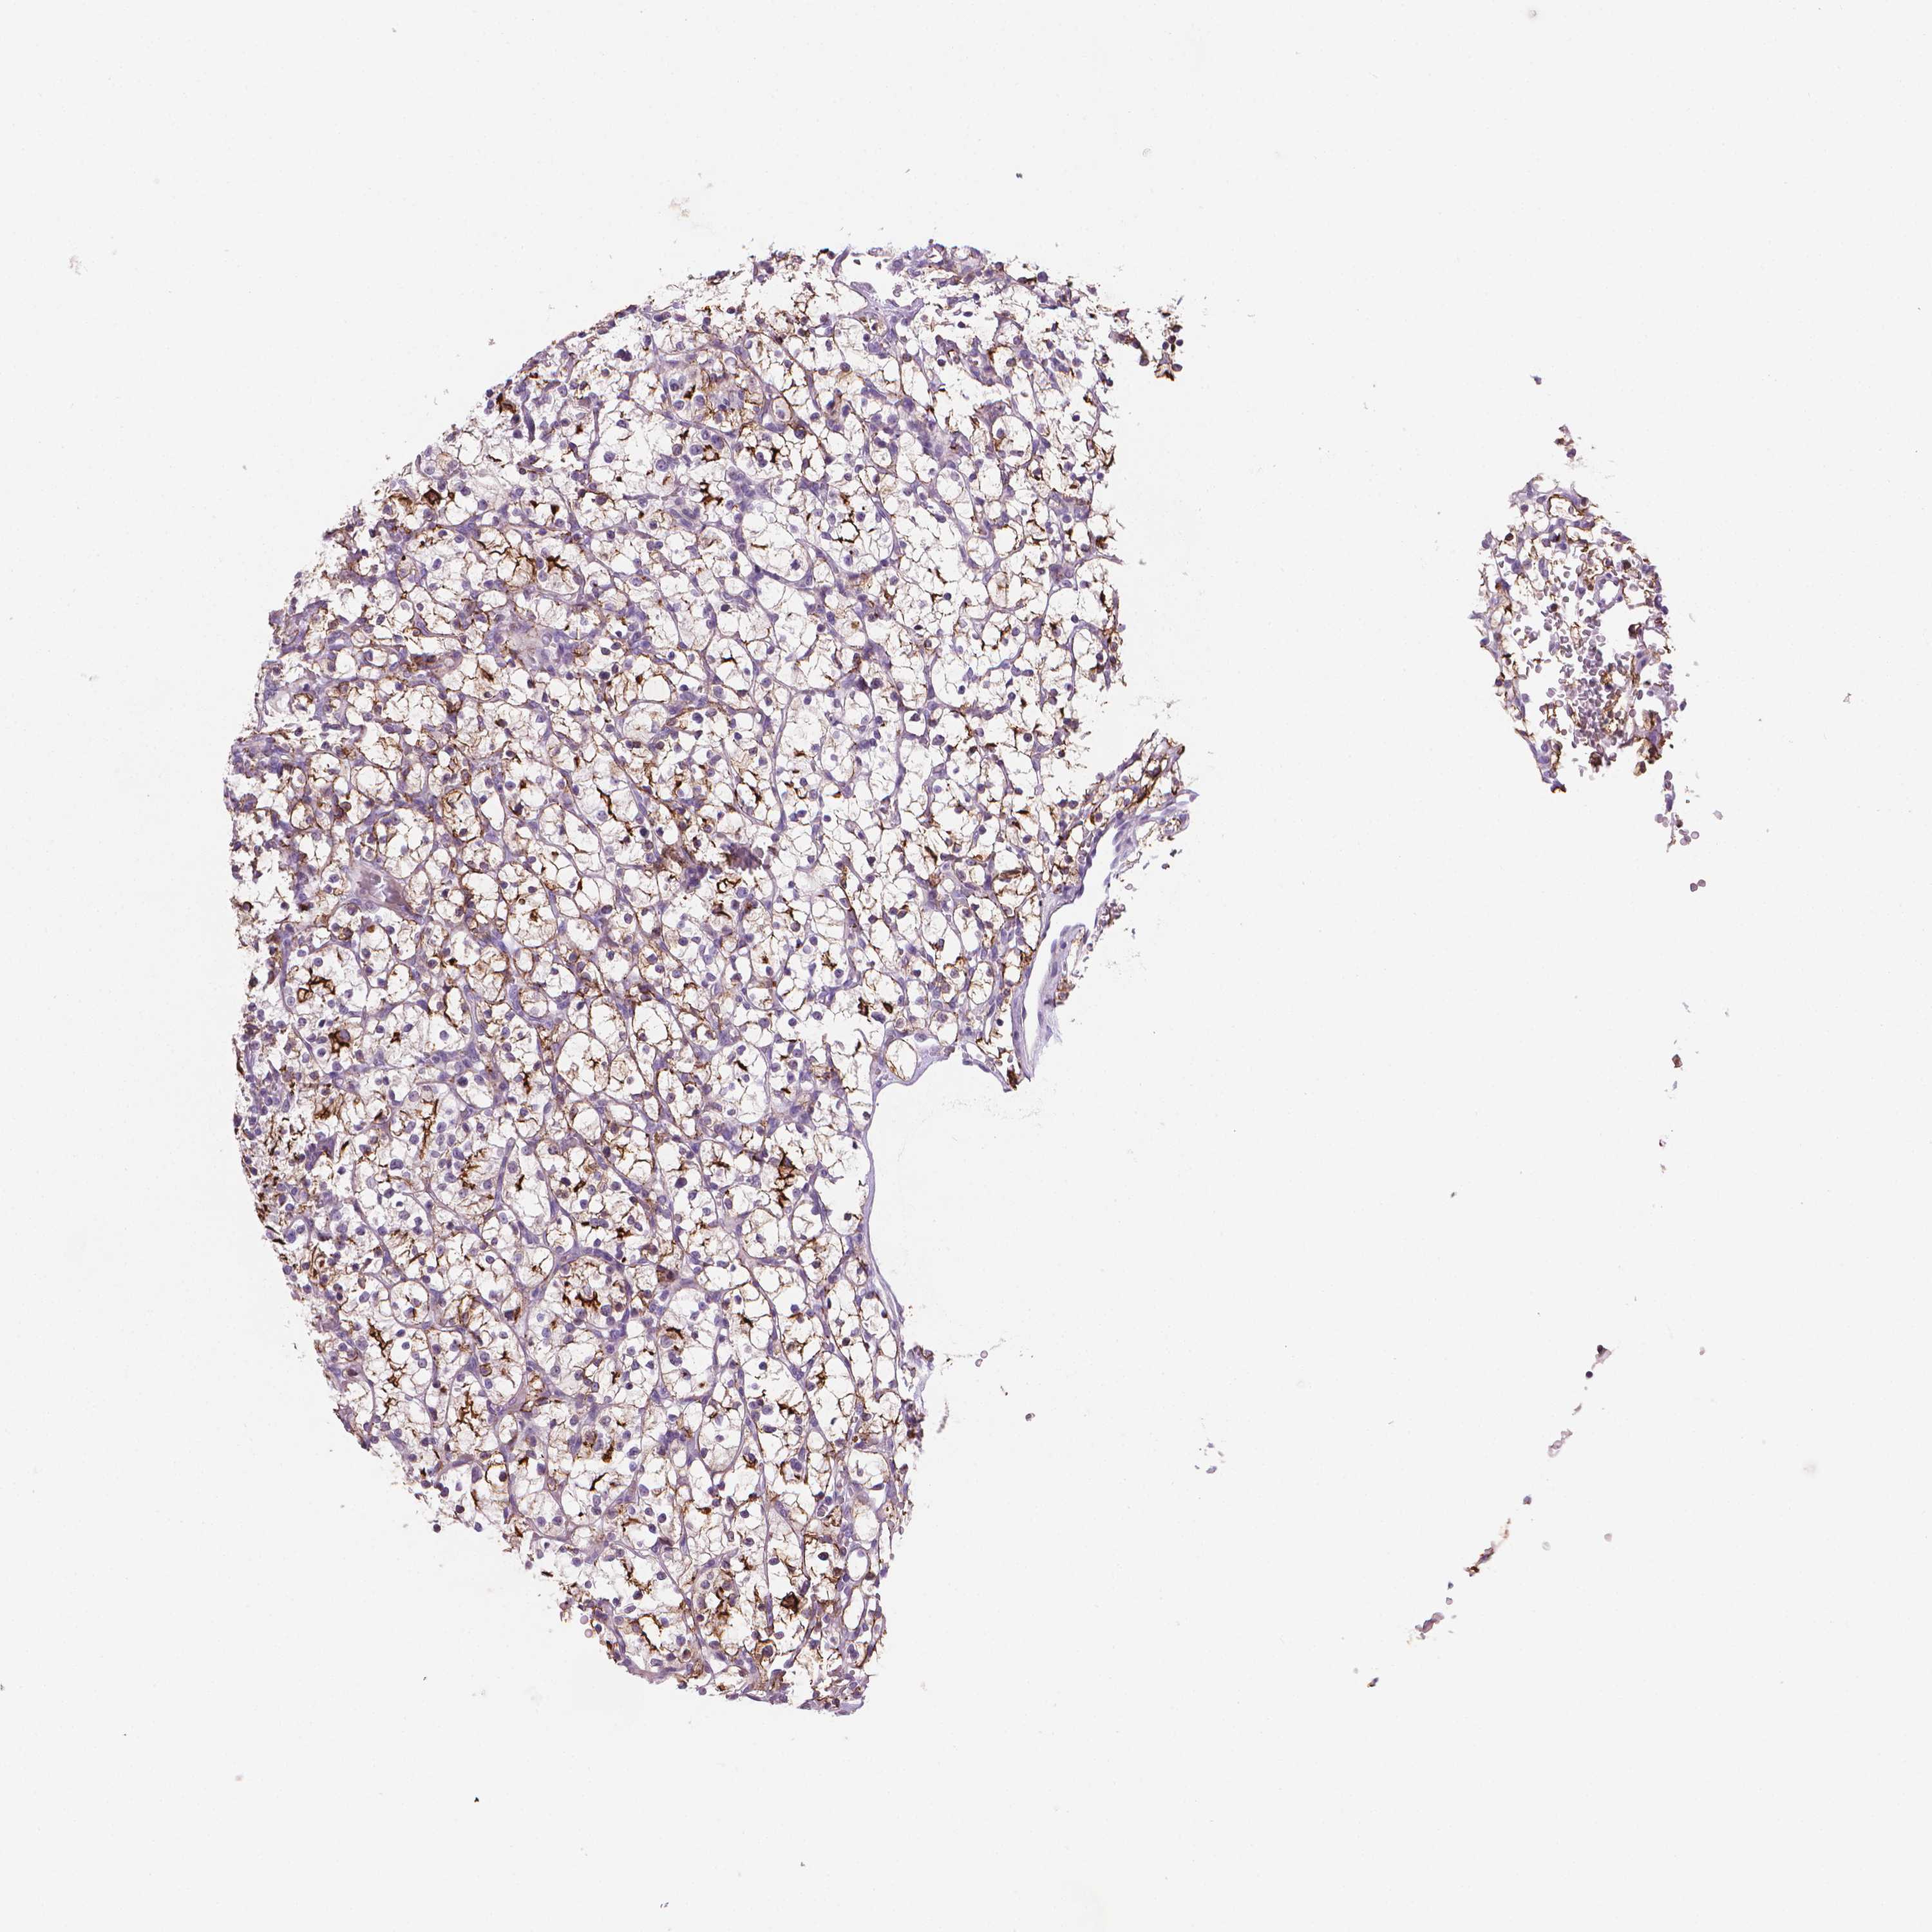

MUC1 is potential prognostic, high expression is unfavorable in Kidney Renal Clear Cell Carcinoma (TCGA)

Best expression cut offi

Based on the FPKM value of each gene, patients were classified into two groups and association between prognosis (survival) and gene expression (FPKM) was examined. The best expression cut-off refers the FPKM value that yields maximal difference with regard to survival between the two groups at the lowest log-rank P-value. Best expression cut-off was selected based on survival analysis .

When clicking on this number, the vertical dashed line indicating cut-off, the interactive survival plot, and the Kaplan-Meier curve will be adjusted to show results based on the best expression cut-off.

: 68.58

P scorei

Log-rank P value for Kaplan-Meier plot showing results from analysis of correlation between mRNA expression level and patient survival.

N/A

TCGA RNA samplesi

RNA-seq data is reported as average FPKM (number Fragments Per Kilobase of exon per Million reads), generated by the The Cancer Genome Atlas (TCGA) .

Normal distribution across the dataset is visualized with box plots, shown as median and 25th and 75th percentiles. Points are displayed as outliers if they are above or below 1.5 times the interquartile range. FPKM values of the individual samples are presented next to the box plot.

Average pTPM 106.2

Number of samples 521